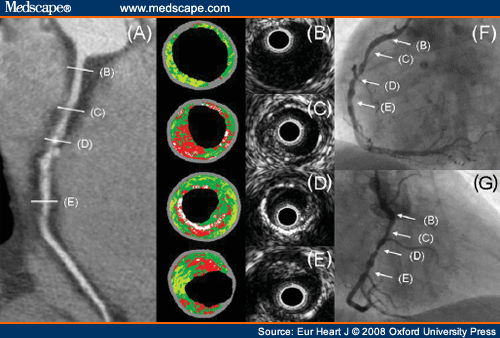

IVUS  يك شيوه تصوير‌برداري از درون رگ توسط امواج اولتراسوند است . مثل اكو كارديوگرافي یا سونوگرافي، كاربرد آن اين است كه تمامي لايه‌هاي رگ را بطور دقيق نشان مي‌دهد در حاليكه در آنژيوگرافي تنها مجرای داخلی رگ توسط ماده حاجب نمایان مي‌شود و به ندرت ممکن است مجرای داخلی رگ در ظاهر طبیعی باشد در حاليكه گرفتاري قابل توجهی در رگ وجود دارد كه آنژيوگرافی قادر به تشخيص آن نيست. لذا تشخيص و انتخاب دقيق سايز بالون و استنت‌ها با IVUS بسيار دقيق‌تر است وعوارض كوتاه مدت و بلند مدت بخصوص پس از Stenting   با IVUS كاهش چشمگير پيدا مي‌كند. يعني ميزان تنگی مجدد Restenosis وایجاد لخته ، انسداد و ساير عوارض کمتر می شود، ضمناً در برخي موارد مثل كار روي تنه اصلی چپLEFT MAIN  ازالزامات قطعي است و با استفاده ازIVUS   نتيجه كار بسيار بهتر و عوارض بسيار كمتر است.

IVUS یکی از روش های تصویربرداری پزشکی است که با استفاده از کاتتر مخصوص که پروب سونوگرافی ریز به انتهای آن وصل شده است، عکسبرداری از لایه عروق انجام می شود.

این روش برپایه ارسال امواج صوتی از طریق کاتتر از داخل لومن رگ به لایه های داخلی رگ و برگشت امواج از همین لایه ها استوار است.تصویر به صورت زمان واقع(  Real Time) بوده و رزولوشن مناسبی دارد.

IVUS با استفاده از تکنولوژی سونوگرافی، رویت لایه های عروق خونی را از داخل لومن رگ فراهم می کند و به این ترتیب بررسی اندوتلیوم(دیواره داخلی) عروق خونی در انسان را امکان پذیر می سازد.

IVUS  برای تعیین اندازه پلاک آتروم در طول شریان های کرونری مورد استفاده قرارمی گیرد.

توضیح: پلاک آتروم در نتیجه پیشرفت تجمع پلاک در عرض دیواره شریان طی دهها سال به دست می آید.این پلاک های آسیب پذیر نهایتاً منجر به تنگی و ضایعه شریانی و حمله قلبی می گردند.

IVUS در تعیین حجم پلاک در دیواره شریان و شدت تنگی لومن شریانی نیز کاربرد دارد.این در حالی است که بررسی موارد فوق به روش آنژیوگرافی غیر قابل اعتماد هستند.

تنگی استیوم شریانی و یا نواحی که در آنژیوگرافی به خوبی رویت نمی شوند و یا رویهم می افتند بوسیله IVUS به خوبی قابل بررسی هستند.

در این روش معمولاً رنگ مجرا به رنگ زرد، غشای خارجی به رنگ آبی و پلاک آترواسکلروتیک به رنگ سبز دیده می شود.

درصد تنگی همانند نواحی لومن به وسیله رنگ مشخص می شود؛ رنگ مجرا زرد و نواحی غشای الاستیک خارجی به رنگ آبی است.